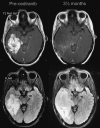

Fig 1.

Pseudoprogression. A 59-year-old man with GBM. An MR image obtained 1 month after RT-TMZ demonstrates an expansion of the right temporal lesion. Reductions in both the enhancing portion and the surrounding abnormal hyperintense area in the T2-weighted imaging were seen in the follow-up MR imaging examinations